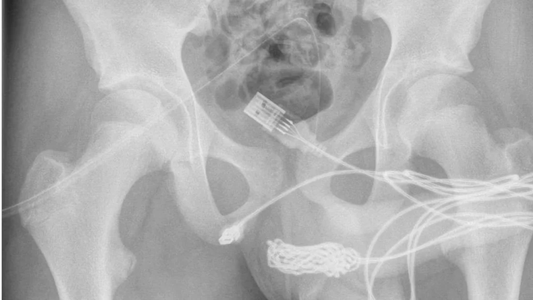

"Se descubrió que los dos puertos distales del cable USB sobresalían del meato uretral externo, mientras que la parte media del cable anudado permanecía dentro de la uretra. El paciente era un adolescente sano y en buena forma física sin antecedentes de trastornos de salud mental”, indicaron los médicos en un informe de ScienceDirect.com.

Los médicos intentaron retirar el cable con una pinza, pero no tuvieron más remedio que practicar una cirugía, muy complicada por los efectos adversos que puede generar una intervención en la zona.

"Se realizó una incisión penoescrotal longitudinal sobre el cuerpo extraño palpable y se realizó una disección cuidadosa a través de los tejidos más profundos, dividiendo el músculo bulboesponjoso", detallaron los expertos al explicar el procedimiento.

Y agregaron: "Ambos extremos del cable se sacaron con éxito a través del meato uretral externo".